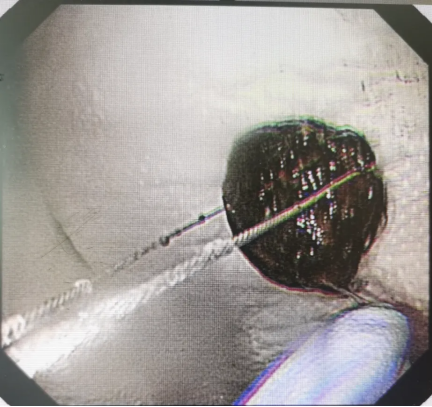

经过术前周密的设计和充分的准备,内镜医师熟练地操作内镜到达十二指肠水平部,但在话梅取出的过程中,正如事先预料的那样,遇到了困难,话梅又短又圆,表面光滑,内镜钳夹后反复滑脱,无法固定住将其取出。

在内镜室医生配合下,经过十几分钟的调整,在十二指肠部位的异物终于无处可逃了,随着医生的动作缓慢向上移动,最终顺利取出。